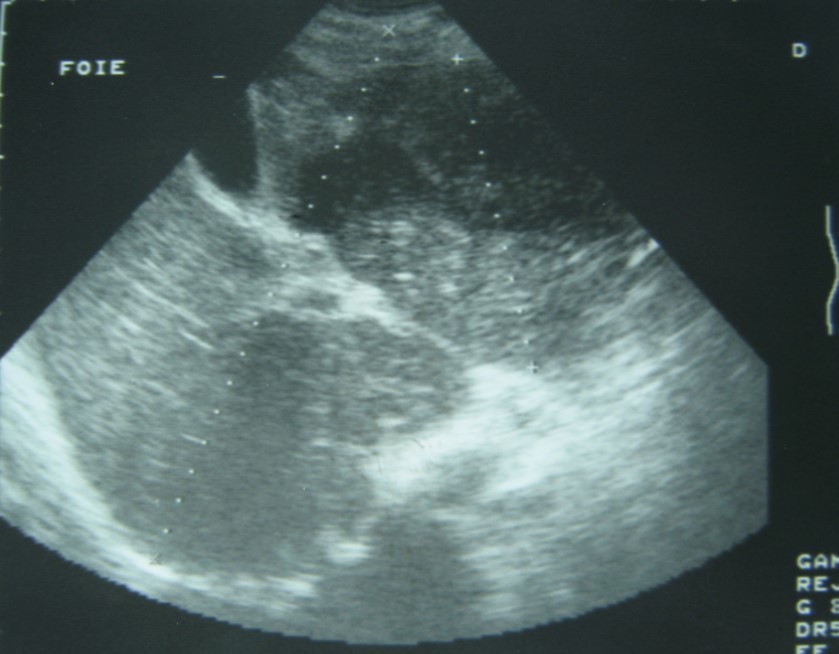

Laboratory analysis showed hemoglobin, 10.9 g/dL; white blood cell count, 9,800 cells/mm3, serum albumin, serum total bilirubin, alanine aminotransferase, aspartate aminotransferase, prothrombin time, hepatitis B surface antigen, and antibodies to hepatitis C, serum alpha-fetoprotein (AFP), carcinoembryonic antigen and carbohydrate antigen 19-9 (CA 19-9) were within normal range. Blood cultures were negative. Chest x-ray was normal. Ultrasound of abdomen showed a 10 cm hypoechogenic lesion in left liver (Figure 1). An abdominal CT showed a well-defined heterogeneous mass situated in his left hepatic lobe measuring 10 cm × 7 cm (Figure 2, Figure 3). The lesion featured central necrosis, a hyper-dense rim and a mild enrichment from the arterial phase in the CT, The diagnosis of primary hepatic tumor was suspected. An ultrasonography-guided needle biopsy of the liver was scheduled in order to rule out malignancy and to have a complete diagnosis. Cytology demonstrated a tuberculosis granuloma, acid-fast bacilli culture was positive (Figure 4). Anti-tuberculous therapy including isoniazid, rifampin, ethambutol, and pyrazinamide were prescribed. The patient completed the 6-month course of medication with success. The patient’s appetite and body weight were restored to previous levels. One year after the completion of treatment, the patient remained completely asymptomatic with disease free.

Figure 2.Abdominal computed tomography with intravenous contrast showing 10x7 cm low-density focal lesion

Abdominal computed tomography with intravenous contrast showing 10x7 cm low-density focal lesion

Computed tomography (CT) and magnetic resonance imaging (MRI) are helpful in diagnosis.

CT findings of tuberculosis abscesses can show low-density focal lesions with or without ring enhancement on contrast administration. These have also been seen in necrotic tumor such as hepatocellular, inflammatory disease and metastatic carcinoma 12.